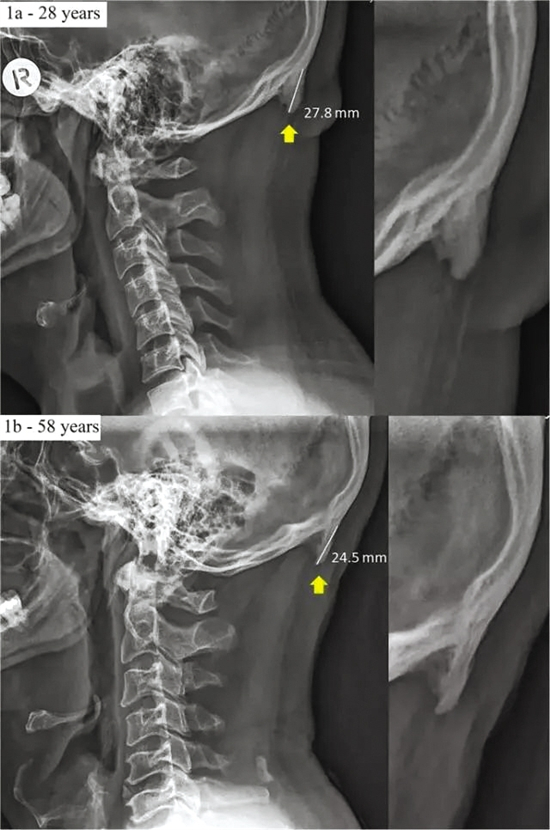

黄色箭头标出的正是后脑勺长出的“刺” (图片来源:《科学报告》)

刊发在国际权威期刊《科学报告》上的一项研究称,澳大利亚学者对1200张成年人X光片进行分析后,已发现有41%的人后脑勺额外长出一根“刺”;还有一项研究整理了医科门诊200多例青少年颈椎X光片后发现,超半数孩子存在颈椎生理曲度不同程度变直甚至反弓现象。

长期不良姿势会改变肌肉骨骼

澳大利亚学者的发现指出,由于经常低头看手机,有些人后脑勺的骨头改变了:一个叫枕外隆突的部位长出来一根“刺”,这些骨刺短的有10毫米,长的居然有30毫米。而其中18岁-30岁的人中,41%的人有这种“刺”。这其实是由于头部不断向前倾斜,重量从脊柱转移至后脑勺的肌肉,导致连接肌腱及韧带的骨骼生长成骨刺,在脖子上方形成一块钩子状或角状的突出骨头。虽然目前不知这种“刺”最终对人体会产生多大影响,不过研究者明确提示:这是长期不良姿势所带来的肌肉骨骼的改变。